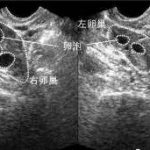

很多女性因为需要做试管婴儿或者是有其他问题需要取卵,但是在取卵之后却发现出现了卵巢囊肿,这是一种不正常的疾病,在出现之后则需要尽快进行控制和治疗,那么取卵后为什么有囊肿?